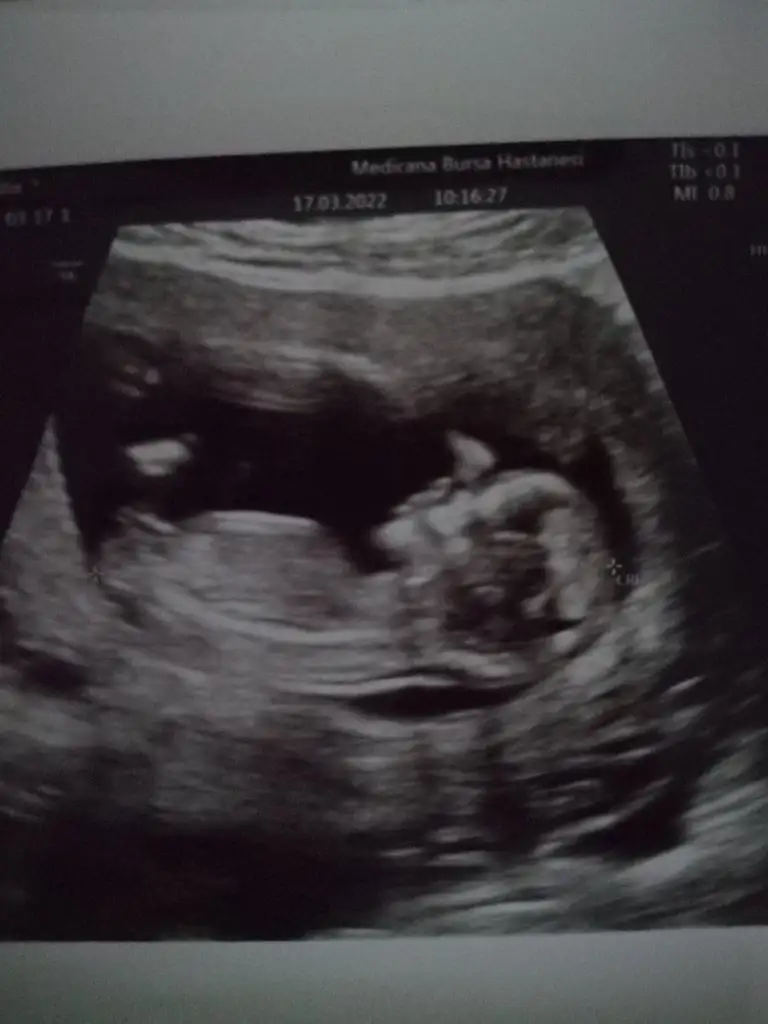

kuzucum nub un yatay bak

Yaa hadi bakalım hayırlısıyla inşallahkuzucum nub un yatay bakbir prenses geliyor

gönlünden geçen olsunYaa hadi bakalım hayırlısıyla inşallahdoktor erkek olabilir ama net değil kızlarda da bu çıkıntı olabiliyor dedi öğrenince haber veririm

karından mı? kaç haftalık?Benim için de tahminde bulunur musunuz?